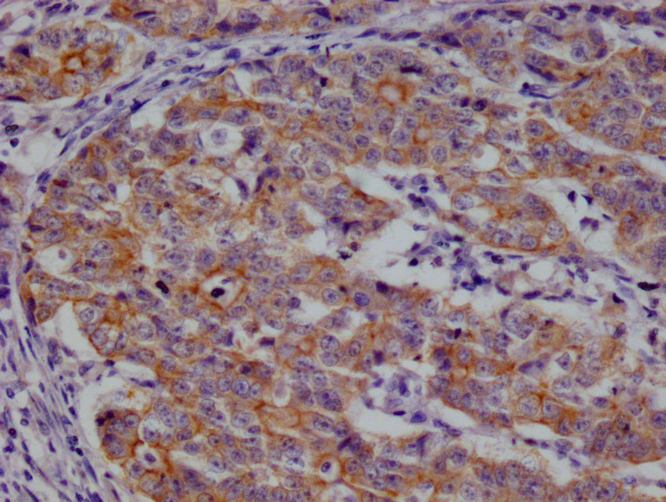

IHC image of CSB-RA959139A0HU diluted at 1:100 and staining in paraffin-embedded human prostate cancer performed on a Leica BondTM system. After dewaxing and hydration, antigen retrieval was mediated by high pressure in a citrate buffer (pH 6.0). Section was blocked with 10% normal goat serum 30min at RT. Then primary antibody (1% BSA) was incubated at 4°C overnight. The primary is detected by a Goat anti-rabbit polymer IgG labeled by HRP and visualized using 0.05% DAB.